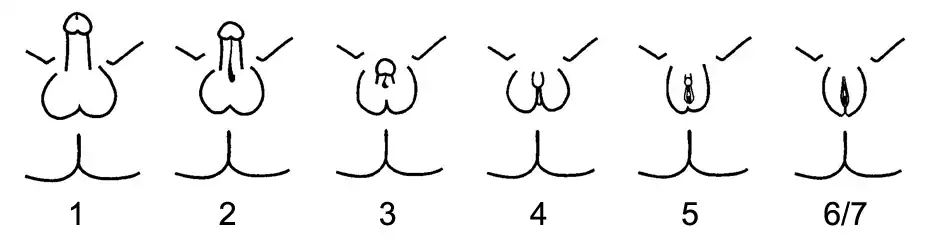

Variations in sex characteristics, also called intersex or disorders in sex development, refer to people with innate genetic, hormonal, or physical sex characteristics outside of medical norms for males or females. It refers to a wide spectrum of variations to genitals, hormones, chromosomes and/or reproductive organs."[1] Intersex conditions can result in a combination of male and female structures, such as having both a womb and testes; atypical genital appearance, such as a closed vagina; or missing or underdeveloped reproductive organs, such as a vaginal opening with no womb.[2] Other characteristics include the presence of micropenis, hypospadias, uretha opening into the vagina, partly fused labia, large clitoris, electrolyte imbalance, undescended testes for males, and masses in the labia or groin for females.[3] Some intersex conditions may result in genitals expected of one's sex, but differing chromosomes (having only an X chromosome, XXY chromosomes, etc.)[2] Up to 1.7% of the general population is estimated to be intersex.[4] The cause of one's intersex variation is often unknown.[2] Some intersex conditions can be inherited from a child's parents; for example, congenital adrenal hyperplasia (CAH) can be inherited if both parents have a copy of the affected gene.[5]

The same intersex condition can have different presentations or severity. Androgen insensitivity syndrome (AIS) has 3 forms: complete androgen insensitivity syndrome (CAIS), partial androgen insensitivity syndrome (PAIS), and mild androgen insensitivity syndrome (MAIS). All forms of AIS include undescended testes. CAIS makes the body unable to respond to androgens, while PAIS and MAIS lead to the body having partial sensitivity to androgens. Those with CAIS present with female genitals but no womb or ovaries and those with MAIS have male genitals but are often infertile. Those with PAIS can present with male genitals, female genitals, or ambiguous genitals.[6]